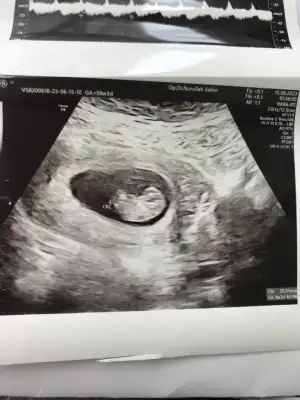

Kizlaaar 🌺 7+2 ye olan uktrasonda erkek kesesine benzeten olmuştu kız diyen olmuştu şimdi burda 9+3üz doktor üç hafta sonra belki olabilir dedi sizin yorumlar nedir 🥰

• 16868210451156612814326109410098.webp

16868210451156612814326109410098.webp

17,7 KB · Görüntüleme: 83